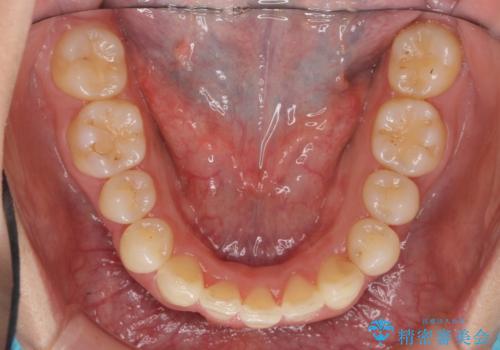

出っ歯 下の歯のガタガタ 下の前歯のみ1本抜歯 マウスピースで1年

下の前歯のがたつきがひどく、非抜歯では難しい状態でした。

古典的な方法では4本抜歯した後、ワイヤー矯正という方法も選択肢には上がりましたが、下の前歯を1本だけ抜くことにし、マウスピースで短期間で治療を終わらせるようにしました。

下の前歯を1本抜くと上下の正中はあいませんが、ほとんど目立ちません。